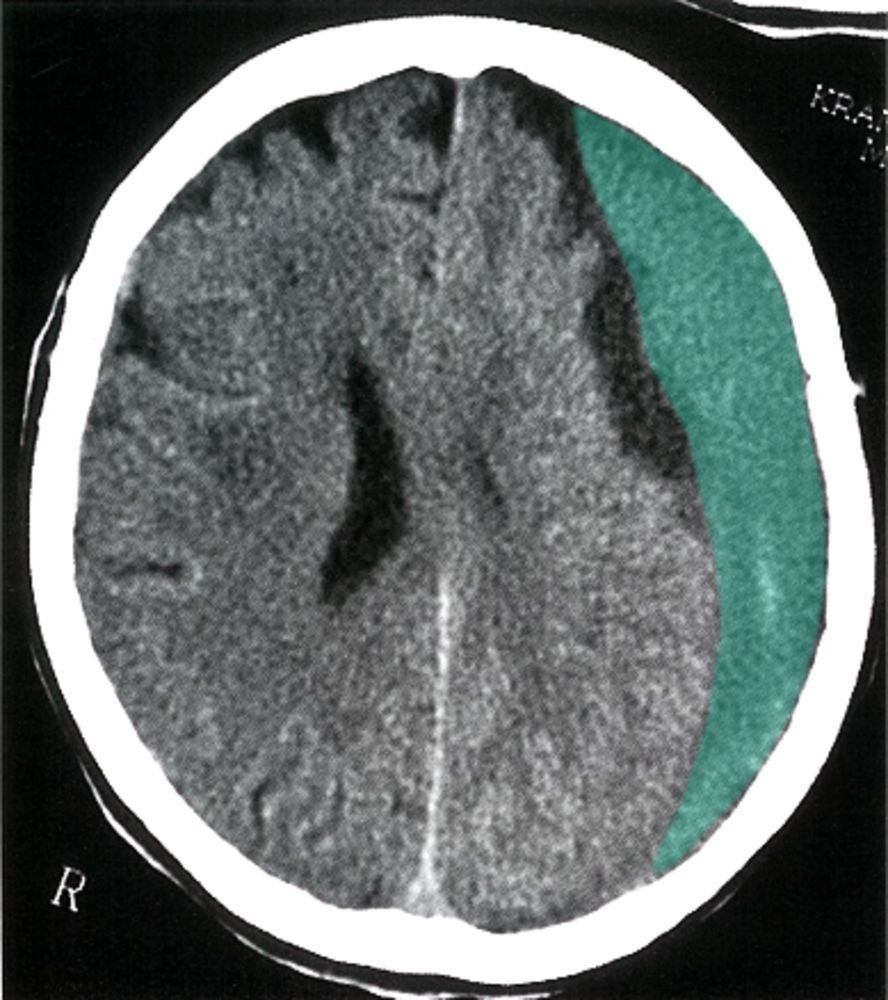

- Chronic SDH is hypodense